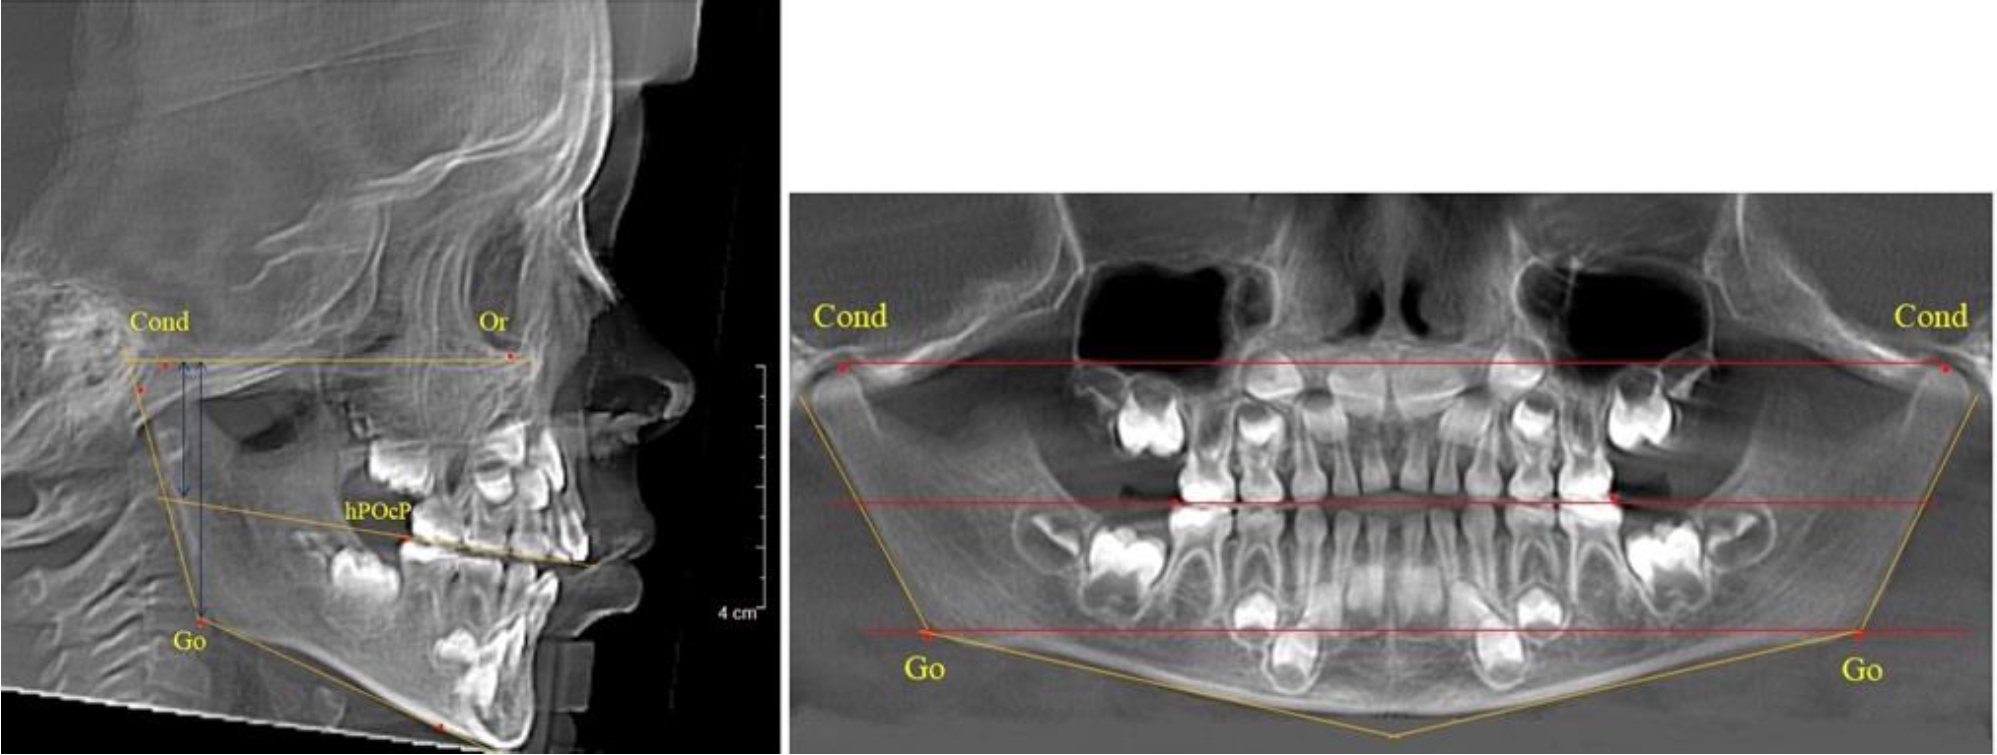

В 3-й группе были проанализированы 9 телерентгенограмм и 9 ортопантомограмм, что составило (8,49 ± 2,71) % от числа изученных рентгенограмм (рис. 3).

Рис. 3. ТРГ и ОПТГ пациента после смены молочных резцов

На всех рентгенограммах произошла смена молочных резцов постоянными. Окклюзионная линия делила ветвь на два отдела.

Высота ветви у детей у детей 3-й группы составляла (51,07 ± 2,72) мм, что было достоверно больше, чем у детей 1-й группы (р ˂ 0,05). При этом высота верхней окклюзионно-суставной части была (29,06 ± 1,44) мм, а нижней – (22,01 ± 1,59) мм. Высота верхней части была больше нижней, что и определяло особенности соразмерности частей ветви нижней челюсти в анализируемый возрастной период.

Относительные показатели соразмерности частей ветви нижней челюсти показали, что отношение высоты верхней части ветви к нижней в среднем составляло 1,32 ± 0,14. Отношение общей высоты ветви к верхней ее части составляло 1,75 ± 0,12, а отношение общей высоты ветви к нижней ее части было 2,32 ± 0,17, что и определяло особенности соразмерности частей ветви нижней челюсти в анализируемый возрастной период.

В 5-й группе были проанализированы 14 комплектов рентгенограмм, что составило (13,21 ± 3,29) % от общего числа. На всех рентгенограммах отмечен очередной этап подъема высоты прикуса, обусловленный прорезыванием вторых постоянных моляров. Окклюзионная линия делила ветвь на два отдела (рис. 5).

Рис. 5. ТРГ и ОПТГ пациента после смены молочных зубов и прорезывания вторых постоянных моляров

Высота ветви у детей 5-й группы составляла (62,87 ± 3,62) мм, что было достоверно больше, чем у детей других групп (р ˂ 0,05). При этом высота верхней окклюзионно-суставной части была (40,23 ± 2,01) мм, а нижней – (22,64 ± 1,78) мм. Высота верхней части была вдвое больше нижней, что и определяло особенности соразмерности частей ветви нижней челюсти в анализируемый возрастной период.

Относительные показатели соразмерности частей ветви нижней челюсти показали, что отношение высоты верхней части ветви к нижней в среднем составляло 1,78 ± 0,18. Отношение общей высоты ветви к верхней ее части составляло 1,56 ± 0,12, а отношение общей высоты ветви к нижней ее части было 2,78 ± 0,14, что и определяло особенности соразмерности частей ветви нижней челюсти в анализируемый возрастной период.